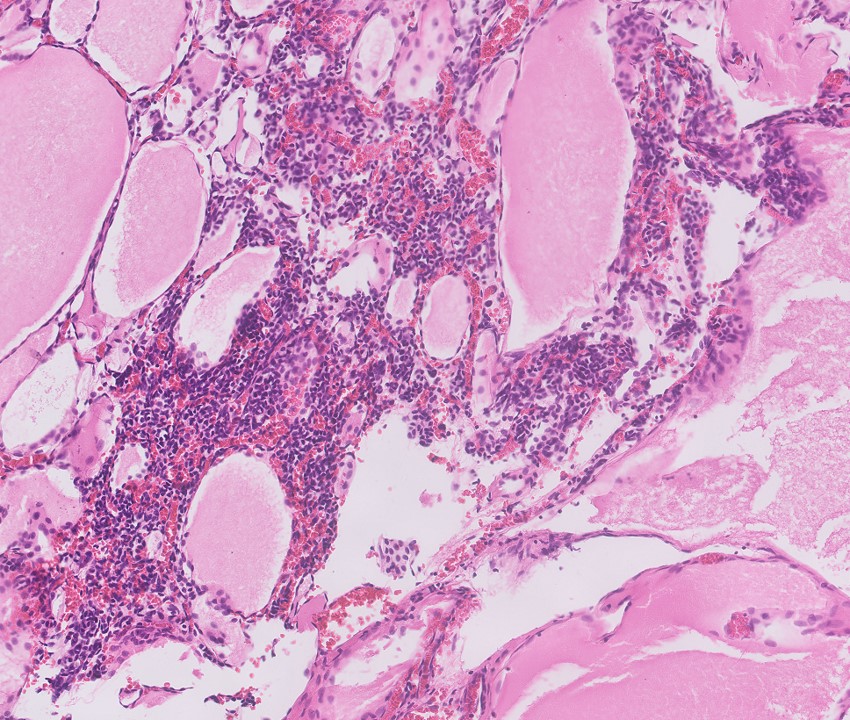

Microscopic (histologic) description

- Cysts lined with flat / cuboidal / hobnail cells (or are denuded)

- Epithelial elements consist mainly of mature and immature / abortive tubules and small papillae resembling immature glomeruli

- Key histological findings of the variably cellular septa include

- Nephroblastomatous epithelial elements

- Islands of undifferentiated blastema and differentiated mesenchymal elements (skeletal muscle and less often cartilage and fat) (J Urol 2010;183:1585)

- Focally, the septal elements may protrude into the cystic spaces in microscopic papillary folds

Microscopic (histologic) images

Contributed by Americo Brilhante, M.D. and Daniel Athanazio, M.D., Ph.D.